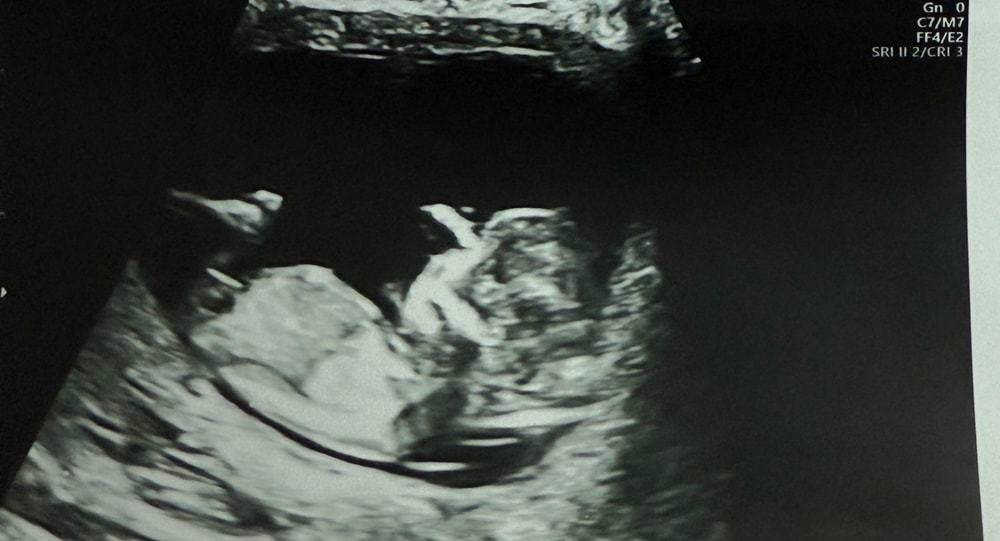

Тут фото головы малыша, как по голове определить пол?

Натали, я в курсе) сама беременна, я о том, что ракурс фото совсем не для определения фото

Алина

Мне кажется девочка. У мальчика как бы шарик на кончике, а у девочки вилочка, или бугорок вообще сужается к кончику. Вот это мальчик 11.1 срок.

Но конечно в 12 недель очень легко перепутать, вот в 13 полных уже лучше видно именно по бугорку, там девочку видно хорошо

На сколько тут смотрела , с таким наклоном встречаются и мальчики и девочки..

Но по-вашему снимку всё-таки девчушка думаю